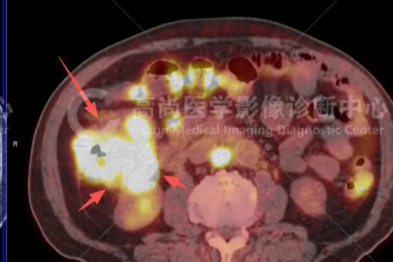

5 个月勇闯生命禁区!包头市肿瘤医院 MDT 团队合力攻坚,成功救治罕见胃癌合并胰腺癌患者!